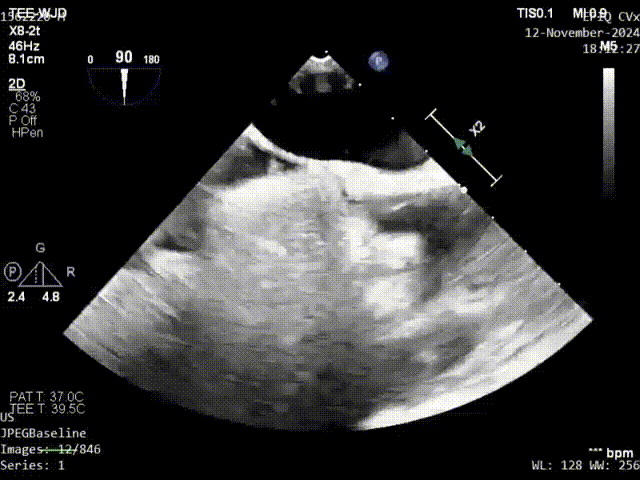

术前发泡影像